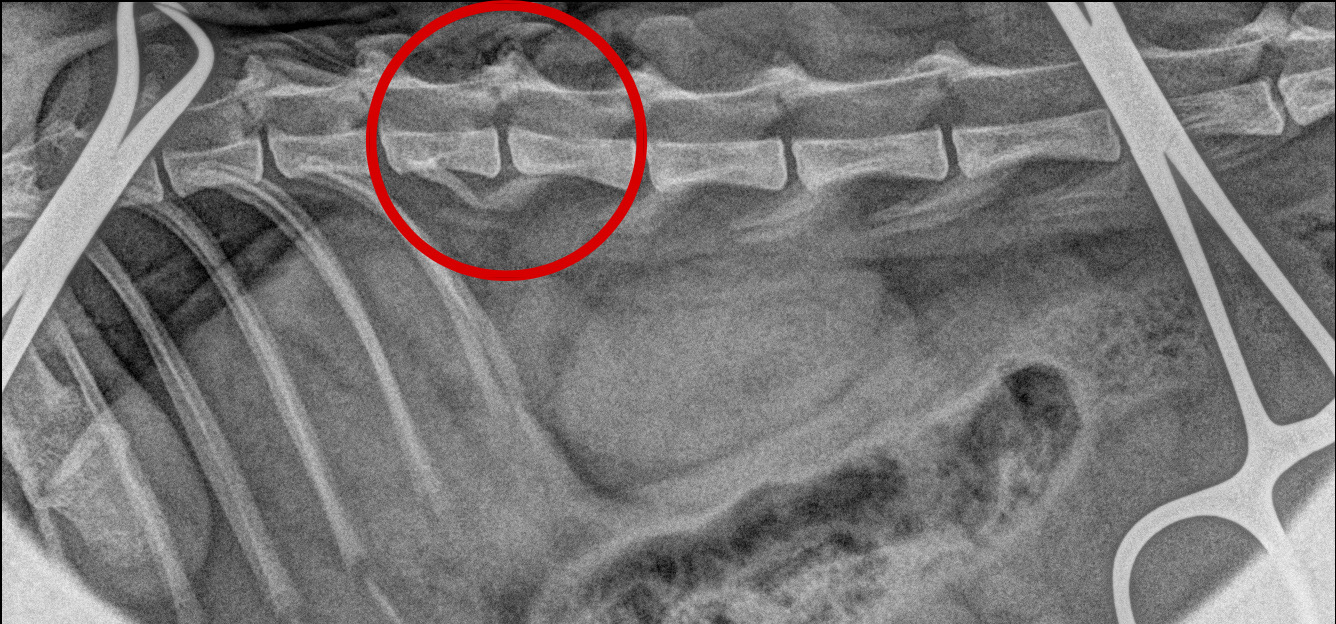

<手術中レントゲン>

脱臼を整復しました。